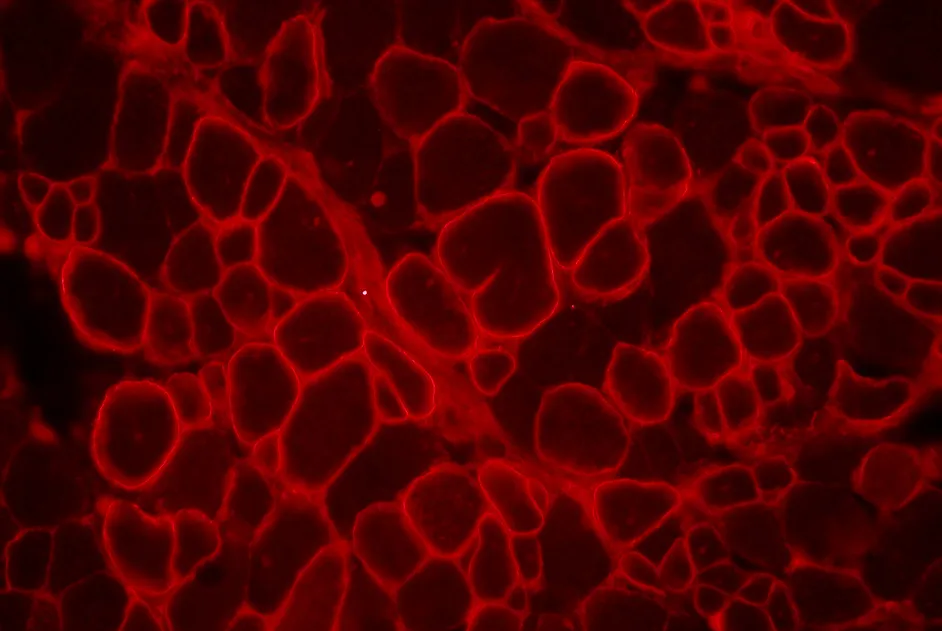

Interactome : un outil pour étudier les protéines des myopathies des ceintures

Généthon a étudié les interactions entre des protéines des myopathies des ceintures et d’autres protéines de l’organisme. Ces liens forment un réseau dense appelé Interactome.